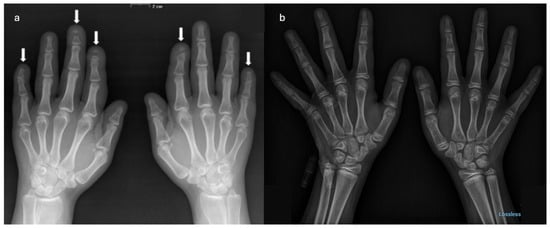

Hajdu–Cheney Syndrome in a Two-Generation Family: Longitudinal Skeletal Progression and Differential Therapeutic Responses in a Mother and Her Son

by Ruggero Lanzafame, Thomas Zoller, Angelo Pietrobelli, Giorgio Piacentini, Rossella Gaudino, Alessandra Guzzo, Giovanni Adami, Francesco Pollastri and Franco Antoniazzi

Hajdu–Cheney syndrome (HCS) is a rare genetic skeletal disorder caused by truncating variants of NOTCH2, characterized by progressive bone resorption and marked phenotypic heterogeneity. Despite advances in understanding Notch signaling in skeletal biology, longitudinal clinical data tracking disease evolution from early childhood through adolescence are lacking. Here, we report a rare longitudinal intrafamilial observation of HCS in a mother and her son carrying the same NOTCH2 pathogenic variant, providing novel insights into disease evolution and therapeutic response. Over extended follow-up, the son exhibited early vertebral fragility despite preserved or supranormal bone mineral density (BMD), whereas the mother developed severe osteoporosis, progressive acro-osteolysis, and multiple vertebral fractures. Longitudinal analysis revealed a dissociation between vertebral fragility and densitometric decline, challenging the paradigm that low BMD is the primary driver of skeletal morbidity in HCS. Treatment responses differed between the two patients, with bisphosphonate therapy in the son associated with stabilized BMD without altering vertebral structural progression, and denosumab in the mother associated with increased BMD, but not preventing progression of acro-osteolysis. Additionally, the emergence of extra-skeletal features during adolescence expands the phenotypic spectrum of HCS and suggests previously unrecognized systemic involvement. These data highlight intrinsic limitations of current therapeutic strategies and emphasize the need for targeted interventions addressing sustained Notch2 activation. Our findings contribute to the understanding of the natural history and therapeutic challenges of HCS, providing the framework for future mechanistic and translational research. Full article

Figure 1